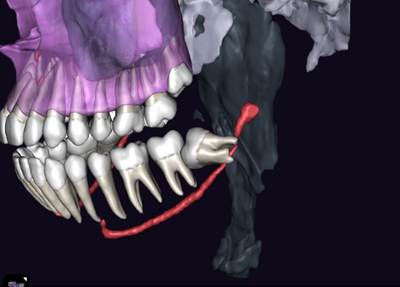

Перед любым лечением мы делаем КТ-снимок челюсти. Дальше в работу включается программа Diagnocat, которая превращает его в детализированную 3D-модель.

Так мы видим нервы, каналы, сложные изгибы челюсти, которые можно не заметить на обычном снимке. На экране можно буквально убрать нижнюю челюсть и посмотреть, как нерв проходит между корнями зуба или где он оказывается особенно близко к потенциально проблемному участку.

Для пациента такая 3D-картинка очень наглядна: вместо того чтобы разглядывать непонятные чёрные полоски на стандартном КТ, он видит полноценную визуализацию.

Если видим такую картину, например, сразу объясняем, что зуб находится в опасной близости к нерву и обычное удаление может быть рискованным.